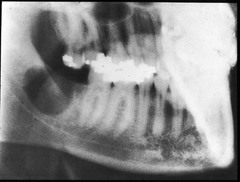

Type of cyst: Follicular cyst; developmental origin; associated with the crown of an unerupted or partially erupted tooth; occurs in 3rd molar area or max. canine area affects mandible more than maxilla

Front

Dentigerous